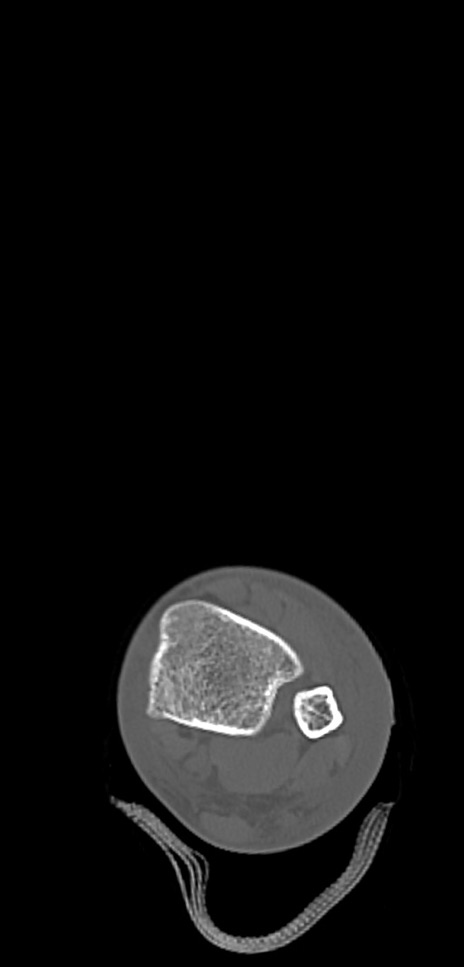

症例37 左足関節CT(横断像)

左足関節CT